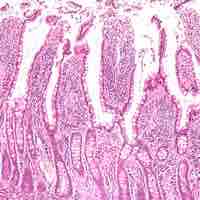

Histology of the Small Intestine

The small intestine wall has four layers: the outermost serosa, muscularis, submucosa, and innermost mucosa.